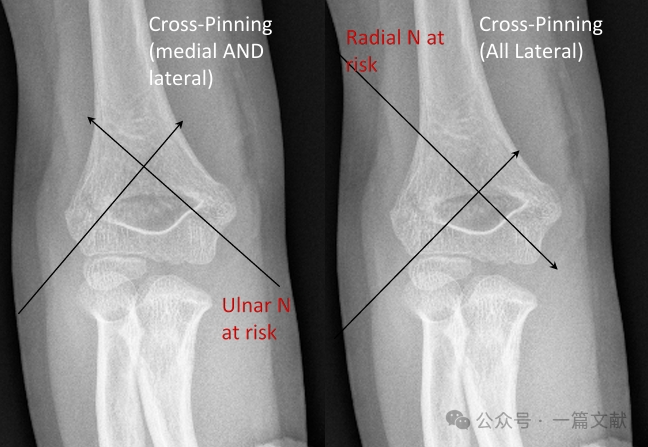

K-Wire Fixation Techniques:

* Cross Pinning (Medial & Lateral):

* Provides biomechanical stability.

* Carries a risk of iatrogenic ulnar nerve injury.

* All-Lateral Pinning (divergent):

* Carries a risk of radial nerve injury.

* Less commonly used.

* Biomechanics: Cross-pinning is the most stable construct biomechanically. However, for most Type 3 fractures, cross-pinning has not demonstrated a clear clinical advantage over lateral-only pinning. Cross-pinning carries a higher risk of iatrogenic ulnar nerve injury (4.3-fold increased risk).

* Indications for Medial Pinning Include:

* Medial comminution.

* Proximal medial to distal lateral oblique fracture pattern (reverse oblique fracture).

* Intra-articular variant fractures. (As shown in the figure).